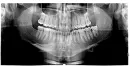

У меня немного опустились десны, только на нижней челюсти, появилась чувствительность к холодному, горячему и сладкому. Дантист сказал, что надо вырывать 4-ку и ставить брекеты и смещать клык на место 4-ки. Не хочется вырывать здоровый зуб. Сделал рентген зубов, разница с 2017 годом нет, но в 2017 году все хорошо было. А сейчас с таким же расположением зубов дёсна опустились. Это началось после удаления зубов мудрости.